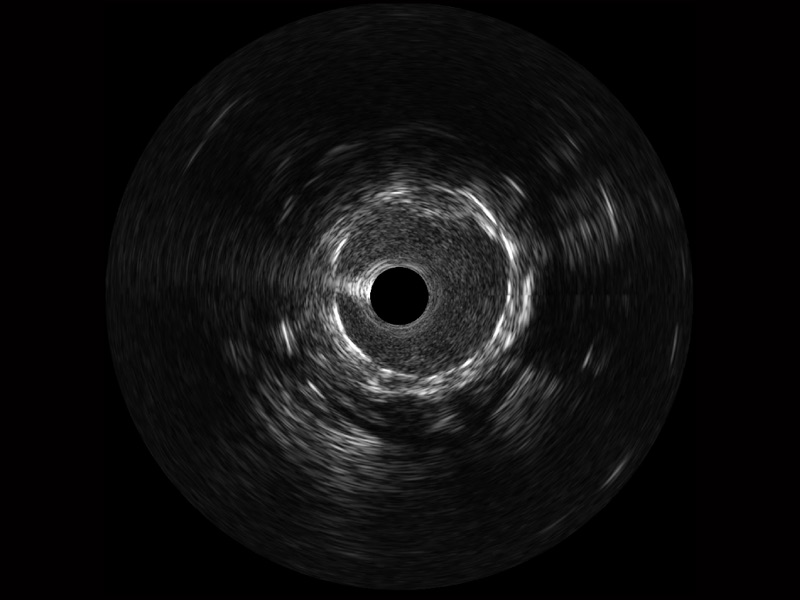

传统IVUS图像

对比传统IVUS导管成像,1xBET宽频IVUS图像的近场支架梁显影更细腻,远场中膜外血管仍清晰可辨,兼顾远中近,兼顾分辨力与穿透深度